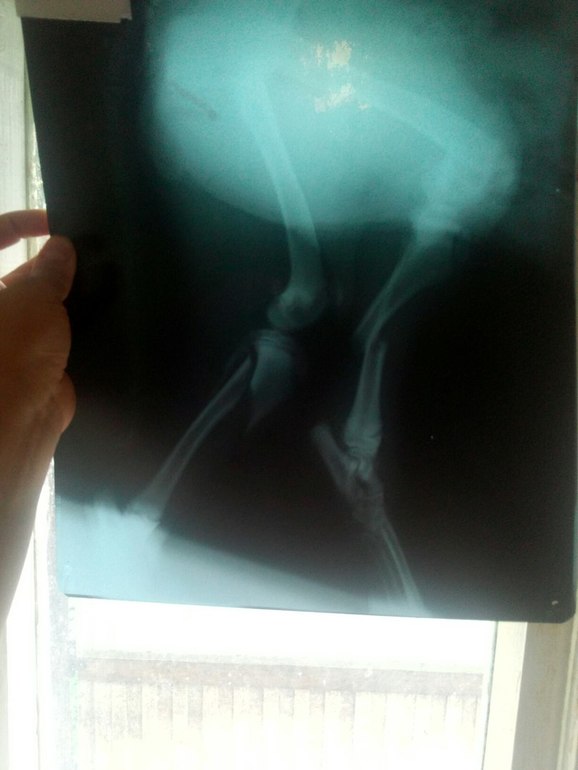

По результатам рентгенологического обследования было выявлено 3 перелома на двух задних лапках.

Был проведен остеосинтез обеих голеней с применением внутрикостной фиксации (штифта). Операция проходила как с использованием общего наркоза, так и эпидуральной анестезии. Общее время операции составило около 3,5 часов.